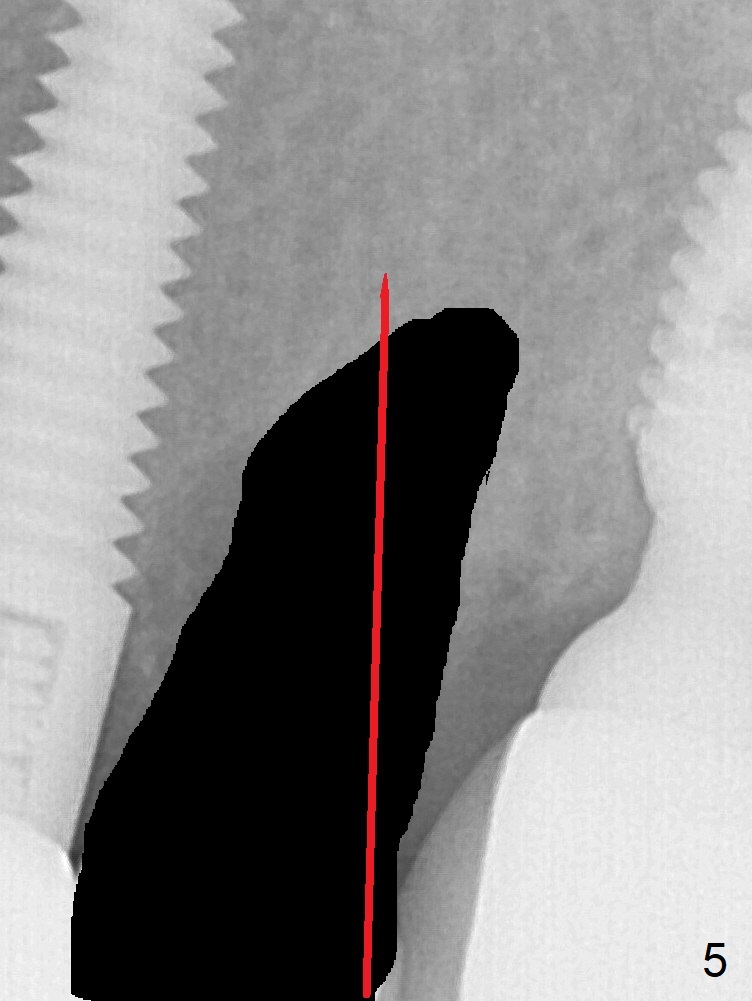

A 59-year-old woman has mild discomfort in the upper left quadrant, which is alleviated by salt water rinse. The buccal gingiva recedes at #13 with mesiobuccal swelling and deep pocket (Fig.1,3), corresponding to the mesial radiolucency (Fig.2 *). The tooth appears to have vertical fractured root, as related to the retention post. Since the root tip curves distal, the initial osteotomy (Fig.5 red) should be established in the mesioapical slope after extraction (black). Following initial entrance, the trajectory will be changed to the long axis of the space (Fig.6) with PA to be taken. Measure the depth of the buccal crest against the buccal, proximal and palatal gingival margins. Place an implant, the same as #12 (4.5x20 mm) unless the mesiobuccal defect is extremely large (UF).